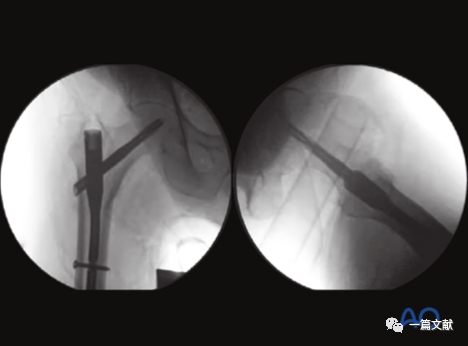

左侧正位片显示颈干角,右侧侧位片显示前倾角。

从侧位片基础上抬C臂机约15°即轴位片,如下:

下图左侧正位片与右侧的轴位片,显示了内固定的良好位置(位于头颈中心与髓腔中心)。需要注意的是这些标准的术中透视图像,只有在良好骨折复位的基础上才能获得。